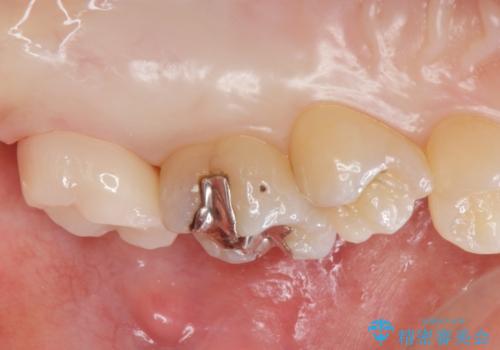

- 奥歯の歯が黒いとの事で来院された患者様です。

頬側の歯の面も粗造になっていたので、インレーではなくジルコニアクラウンでの治療となりました。